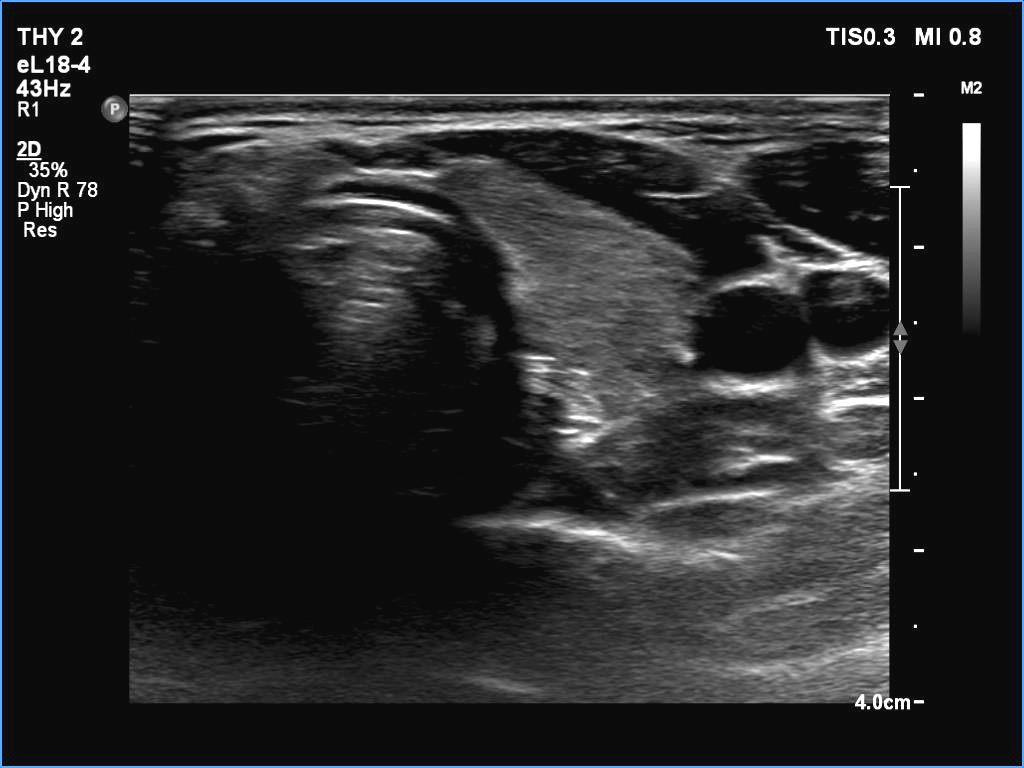

Ultrasonography. The thyroid was echonormal. There were two partly deeply hypoechoic nodules, one in the ventrolateral part of the right lobe and another one in the isthmus. Both had irregular margins and punctate echogenic foci. There was a mirror image artifact of the lesion in the isthmus.

Both nodules had multiple suspicious features: beside deep hypoechogenicity and irregular borders, microcalcifications should be also considered. The nodule in the right lobe presented also three possible sonographic signs of a possible extrathyroidal spread: the pseudocapsule of the thyroid was not intact, the lesion had both abutting and butting contours.